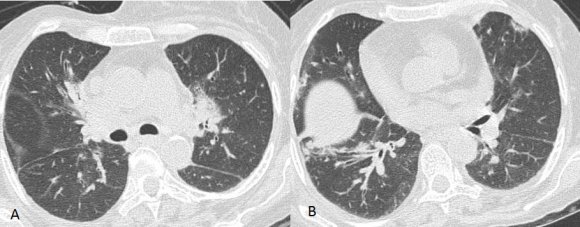

Computed axial tomography (CT scan) of the thorax (Figures: 1-3) showed small patchy areas of alveolar consolidation in the peripheral portion of the right middle lobe and lingula, and the left perihilar region. Multiple small nodular lesions were noted in the peribronchial region in the anterior basal segment of the right lower lobe and segmental bronchi of lingula. Multiple lymph nodes of size 5 to 10 mm were noted in pretracheal, right paratracheal, subcarinal region, in prevascular space and aortopulmonary window. Bilateral axillary lymph nodes also noted, the largest right axillary lymph node measured 13x13mm. Most of the lymph nodes showed peripheral enhancement with central hypodense areas of necrosis. Lymph nodes were also noted in the right juxtadiaphragmatic region, the largest measuring 13x9mm. There was no pleural effusion on either side.

Figure 2. Figure 1 :Figure 2 :

12Figure 1: HRCT of thorax showing patchy areas of alveolar consolidation in the right middle lobe, in lingula (A) and multiple small nodular lesions in the peribronchial region in the anterior basal segment of the right lower lobe.(B)